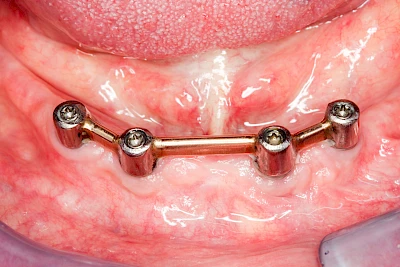

Bei herausnehmbaren Prothesen werden Implantate eingesetzt, um den Halt und den Tragekomfort der Prothesen zu verbessern. Dazu kommen verschiedene Verbindungselemente zum Einsatz:

- Teleskope

- Kugelköpfe

- Tellerförmige Lokatoren

- Stege

- Magnete (selten)

Varianten zur Verankerung von abnehmbarem Zahnersatz auf Implantaten